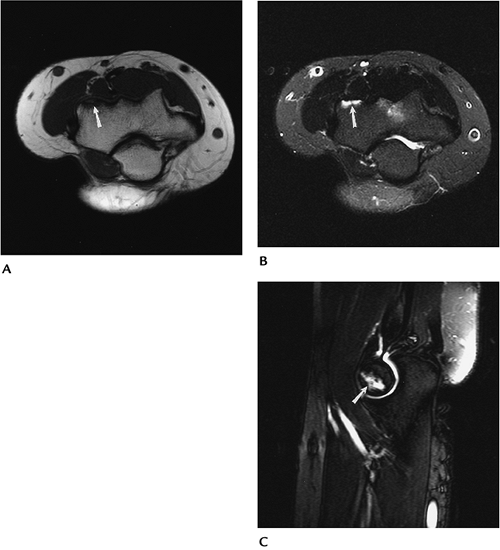

P.537

![]() |

FIGURE 8-18 Axial T1- (A) and fast spin-echo T2-weighted (B) with fat suppression and sagittal fast spin-echo T2-weighted (C) fat-suppressed images demonstrate an undisplaced osteochondritis dissecans of the capitellum (arrow).